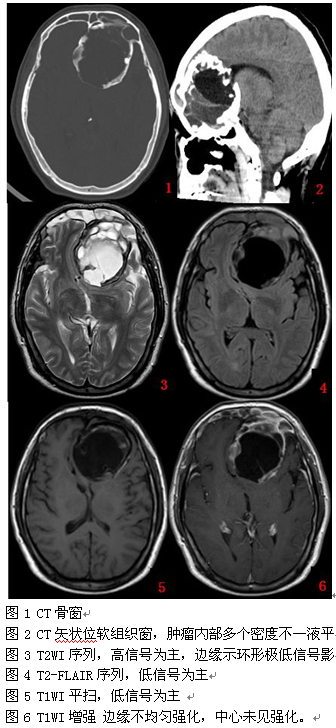

CT示左侧前颅窝底一较大占位性病变,向下累及左侧筛窦及蝶窦,左侧筛窦呈膨胀性改变,左侧眼球受推压前移。病变周围可见硬化边,其内密度不均,部分呈明显低密度,部分呈稍低密度,其内可见多个分隔,部分分隔可见点状高密度影。病变边界清晰,范围约为7.37cm×6.39cm×7.00cm,周围脑组织受推压。考虑骨源性肿瘤可能。

MR示前颅窝底偏左侧一较大的囊实性占位性病变,囊性部分较大,呈长T1长T2信号,FLAIR序列呈稍高信号,实性部分呈等T1短T2信号,FLAIR序列呈稍低信号,增强后,病变呈不规则环形强化,其内可见多个分隔,范围约为7.05cm×5.20cm×7.27cm。病变周边可见极低的含铁血黄素影,边界清晰,向下累及左侧筛窦,左侧内直肌明显受推压,病变边界清晰,周围未见明确水肿信号影。考虑偏良性病变,骨源性肿瘤可能性大。